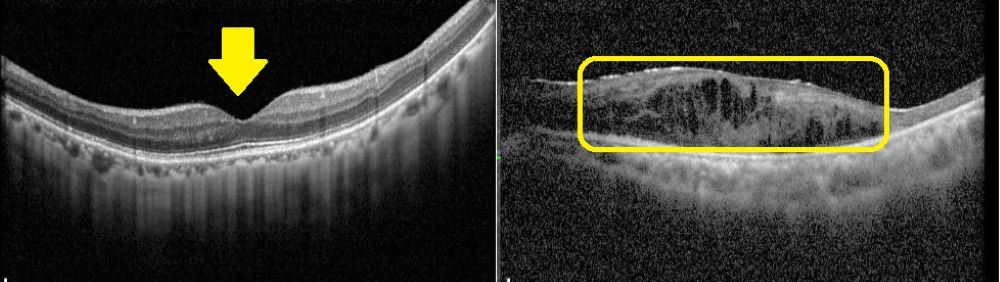

賴旗俊指出,黃斑部病變分為乾性與濕性兩類,乾性病變約佔8成,病程進展慢,目前無特效藥,只能靠改善生活習慣延緩惡化,如配戴太陽眼鏡防止強光照射、戒菸、控制三高、補充抗氧化營養素等;濕性病變惡化速度快,主要是由新生血管異常增生造成出血與水腫,需透過眼內玻璃體注射抗血管新生藥物治療。

若符合健保給付標準,單眼最多可施打14劑眼內注射藥物,臨床顯示約8成患者連續注射3劑後,3個月內視力可改善;但若延誤治療,95%的濕性患者在2年內可能造成失明,因此及早診斷與介入治療至關重要。